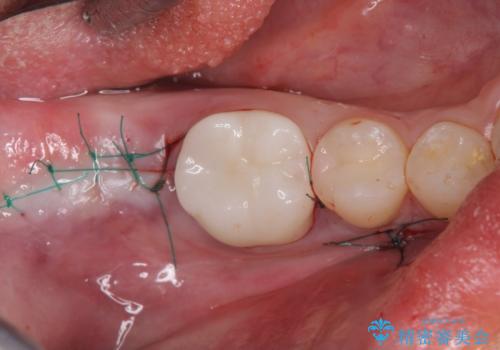

今回はかぶせ物の高さを確保するために、少し顎骨を削り、歯肉の厚みも薄くしました。

- 外科手術のため、術後に痛みや腫れ、違和感を伴います